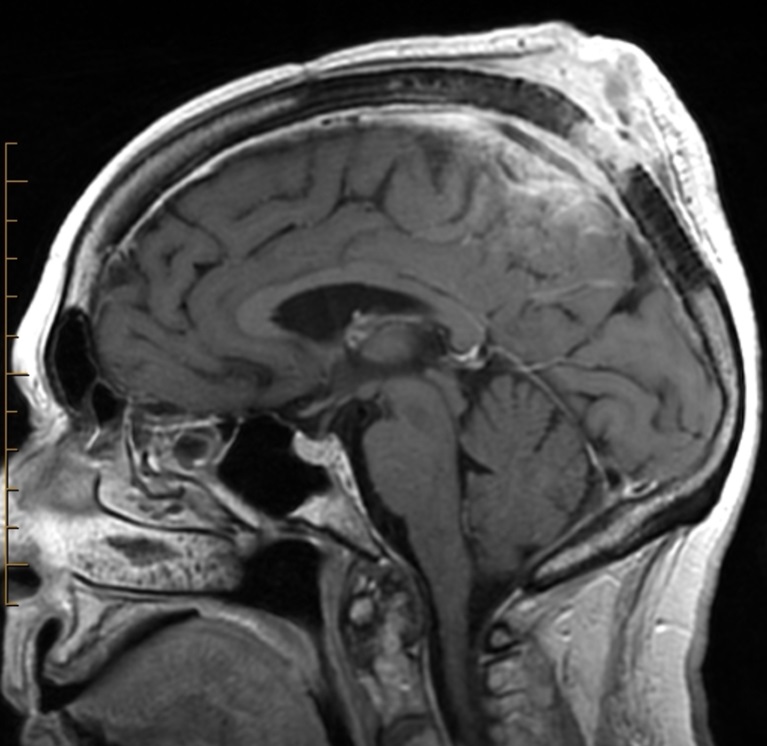

Mặc dù không phải công cụ thường quy cho chẩn đoán ban đầu, hình ảnh học vẫn cho thấy sự hữu ích trong đánh giá mức độ xâm lấn hoặc di căn.

- Công hưởng từ (MRI): phù hợp khi nghi ngờ xâm lấn xương, mô mềm sâu; cho độ phân giải mô mềm cao, đặc biệt quan trọng trong SCC và melanoma có xu hướng phát triển xâm nhập.

- Chụp cắt lớp vi tính (CT): hỗ trợ đánh giá giai đoạn, phát hiện hạch bạch huyết to hoặc di căn xa (phổi, gan, xương), thường áp dụng trong SCC và melanoma tiến triển.

Hình ảnh MRI một trường hợp ung thư biểu mô tế bào vảy vùng đỉnh đầu xâm lấnHình ảnh MRI một trường hợp ung thư biểu mô tế bào vảy vùng đỉnh đầu xâm lấn